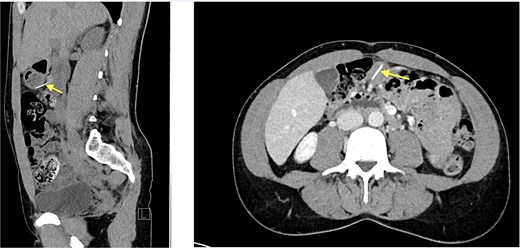

Eventually, diagnostic laparoscopy showed a small posterior gastric perforation next to the liver abscess with migration of the metal bristle into the liver, causing the abscess. Consecutively, surgical drainage of liver abscess, recovery of the foreign body, and gastric perforation repair with sutures were performed (Fig. 4). No postoperative complications occurred. The patient received intravenous antibiotic treatment for 10 days, followed by oral antibiotics for another 4 days. Follow-up showed decreasing CRP and WBC and rapid recovery after surgery. On the 4th postoperative day, the patient could be discharged.